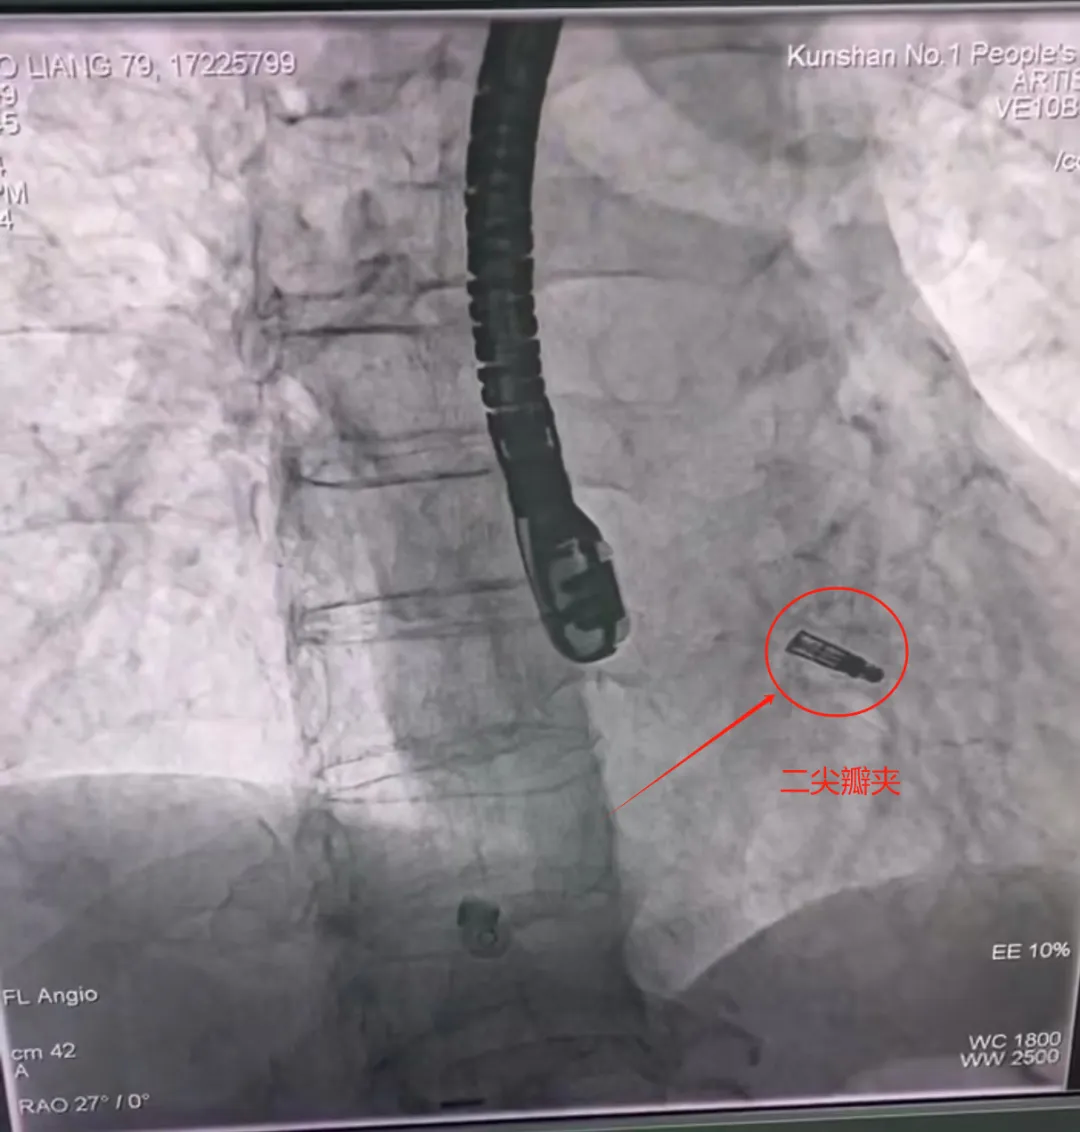

行“经导管二尖瓣钳夹术”

68岁的李先生

和79岁的庞先生

均存在二尖瓣重度返流

血液在心脏里来回移动而不泵向身体

导致心脏负担明显增加

经昆山市一医院多学科讨论

制定治疗方案

行经导管二尖瓣钳夹术

市一医院心胸外科主任医师张亚年:

“该手术无需开胸,

相对体外循环下的心脏手术,

该手术仅腹股沟1cm穿刺切口,

创伤较小,恢复快。”